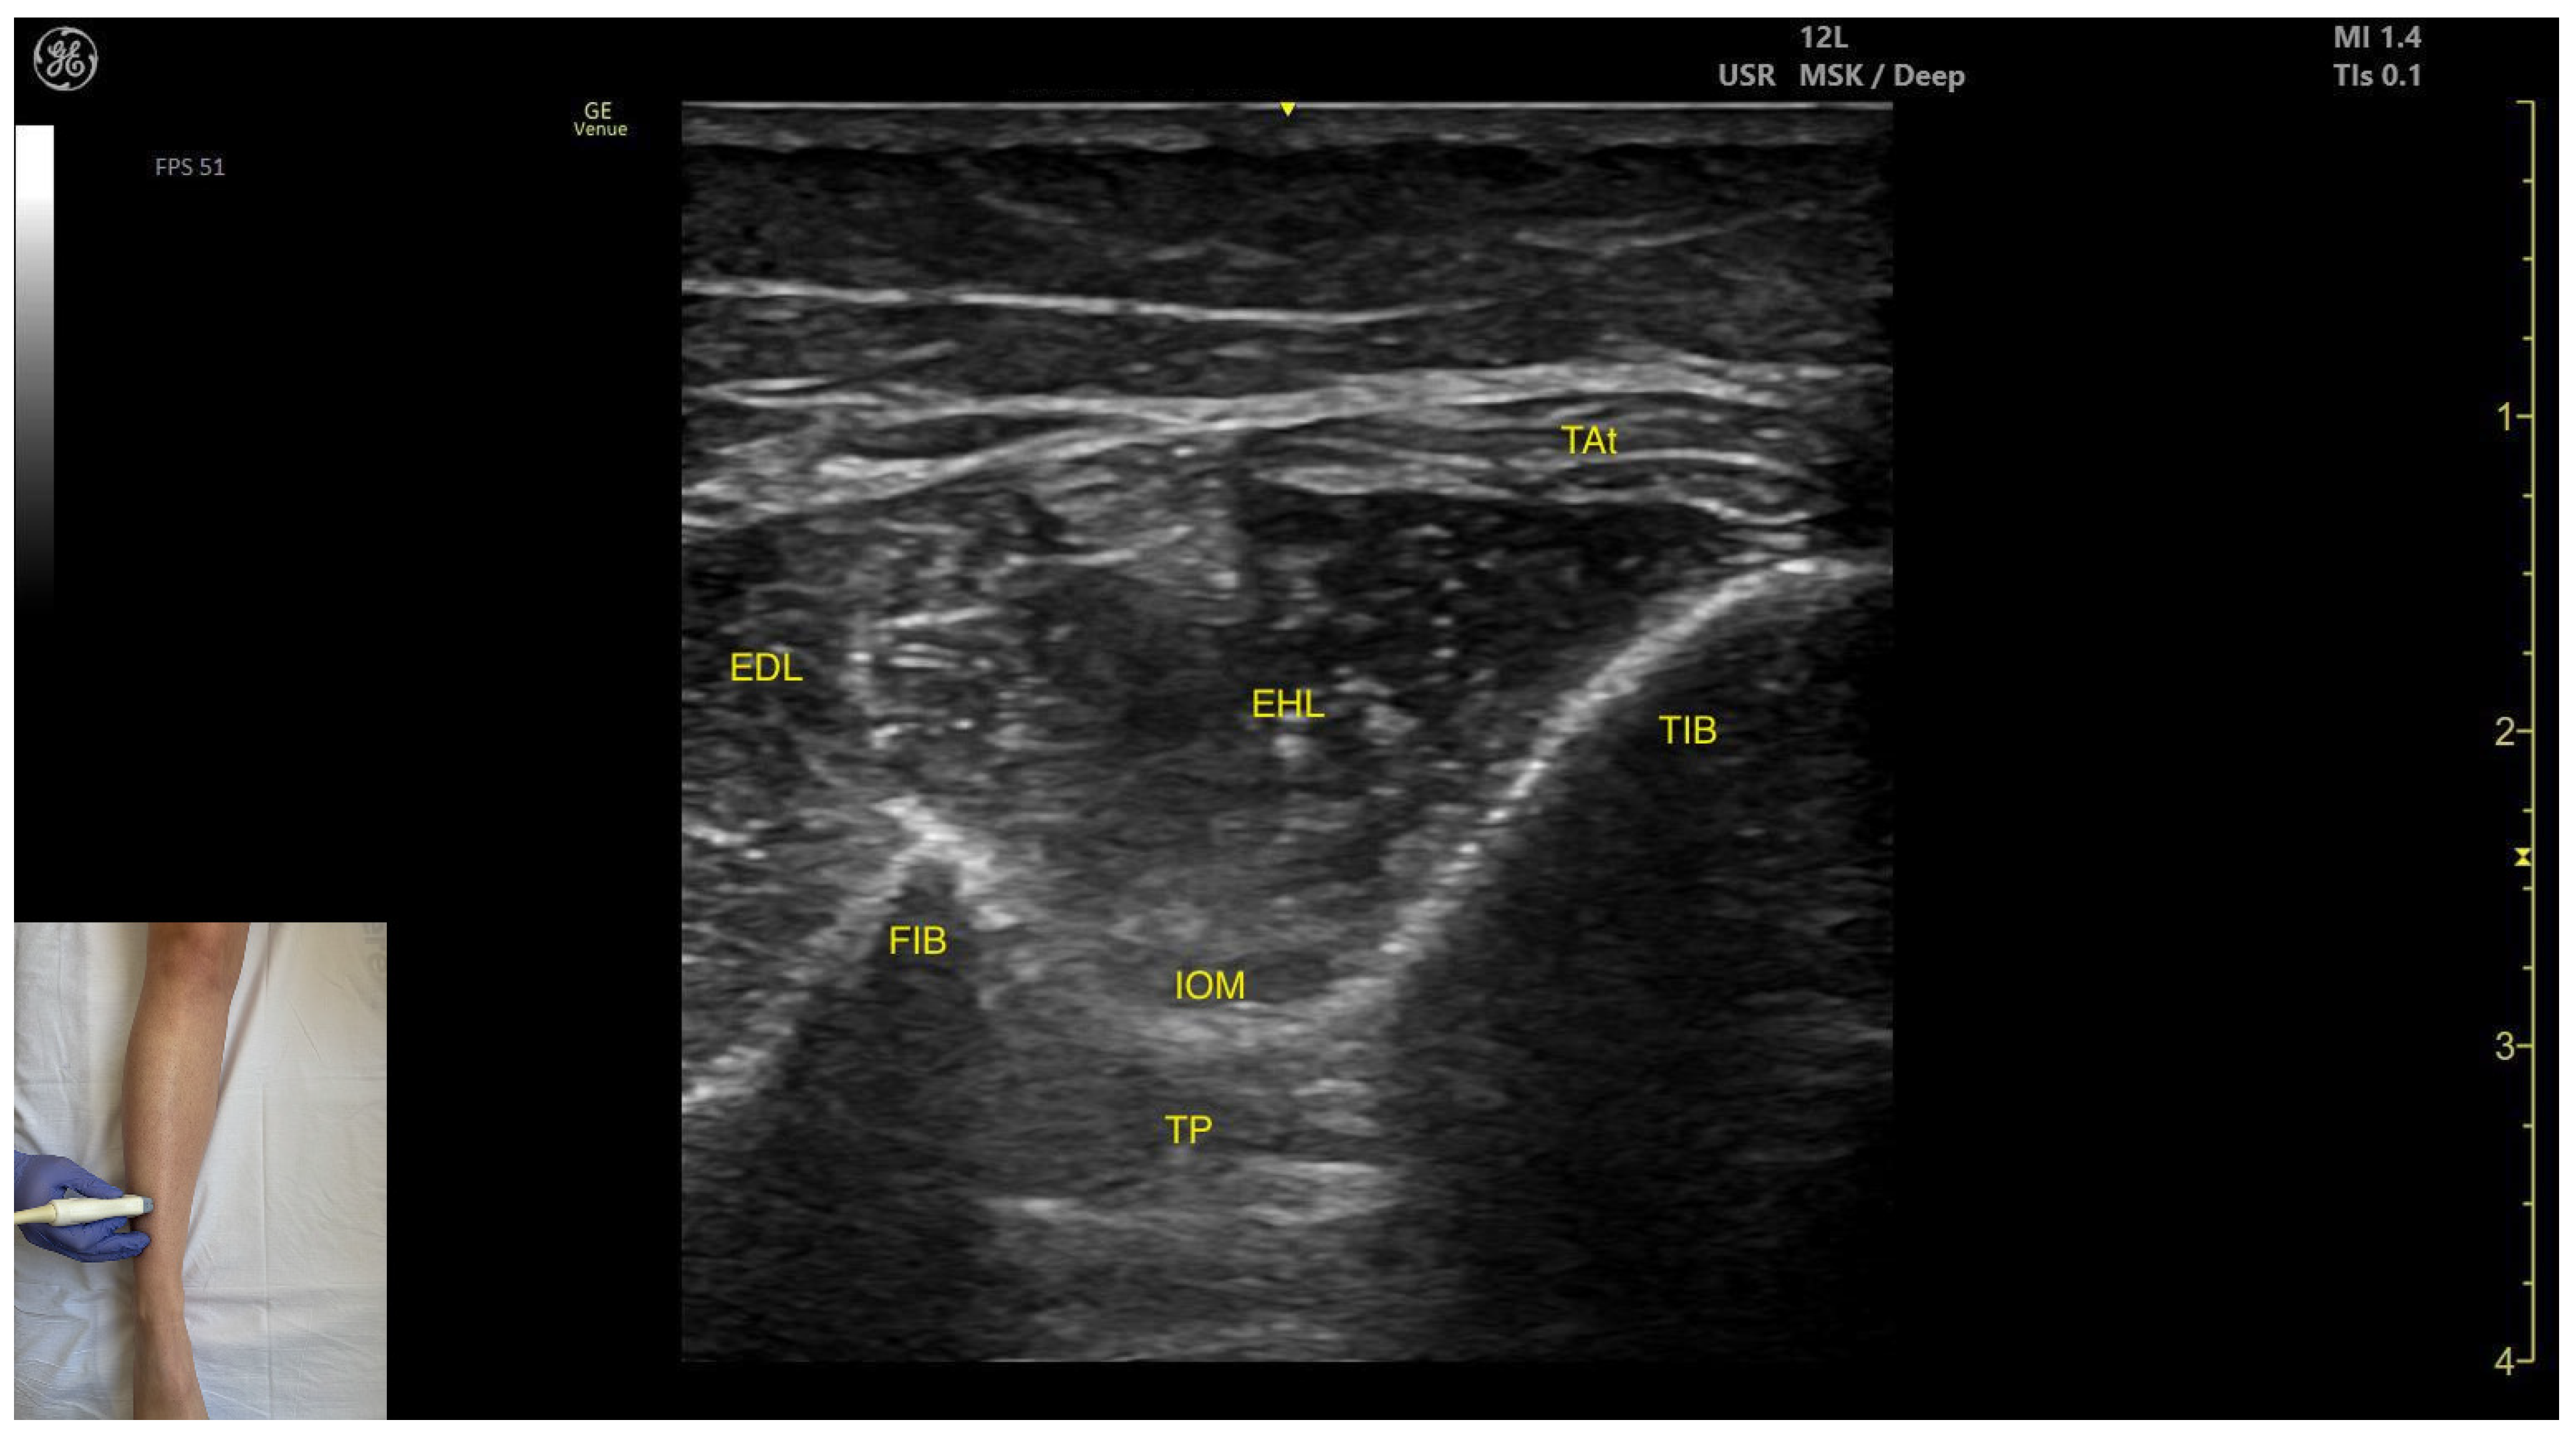

- Muscle position: It is the deepest muscle in the posterior compartment of the leg.

- Neurovascular bundle: Superficial to the interosseous membrane lies the neurovascular bundle composed of the deep peroneal nerve, anterior tibial artery, and anterior tibial vein.

- External fascia: TP has a pronounced fascia that separates it from the tibialis anterior and extensor digitorum longus during BoNT-A injection.

- Dynamic evaluation: During dynamic evaluation muscle contraction is visible during inversion and plantar flexion of the ankle joint.

- Muscle position: It appears as a superficial muscle mass. Deep to the TA lies the interosseous membrane separating it from the tibialis posterior; the extensor digitorum longus lies lateral to the TA.

- External fascia: The TA does not feature a pronounced fascia that separates it from extensor digitorum longus, during BoNT-A injection.

- Dynamic evaluation: During dynamic evaluation, scanning distally toward the ankle, the tibialis anterior decreases in thickness as it transitions into its tendon. Muscle contraction is seen during plantar dorsiflexion and inversion of the ankle joint.

- Muscle morphology: It is an unipennate muscle.

- Muscle position: It appears as a superficial muscle mass at this level. Laterally, the extensor digitorum longus (EDL) is visualized; superficially and laterally is the tendinous portion of the tibialis anterior (TA). Deep to the EHL lie the interosseous membrane and the tibialis posterior (TP).

- External fascia: The ELH does not have a well-defined fascia that separates it from the subcutaneous plane, the extensor digitorum longus, tibialis anterior. The interosseous membrane separates the EHL from the tibialis posterior, during BoNT-A injection.

- Dynamic evaluation: During dynamic evaluation, scanning proximally toward the knee joint shows a reduction in EHL muscle thickness with a concurrent increase in tibialis muscle thickness (Video S3). Muscle contraction is visible during hallux extension at the metatarsophalangeal and interphalangeal joints and during dorsiflexion at the ankle joint. It is clinically relevant in relation to the Babinski sign, often referred to as the “hitchhiker’s great toe,” which is characterized by dorsiflexion of the hallux in response to stimulation of the plantar surface of the foot.

| Tibialis Posterior (anterior window) | ~10 cm distal to the knee joint, in the lateral portion | Interosseous membrane, deep fibular nerve, anterior tibial artery, and anterior tibial vein (superficial); tibialis anterior (superficial and medial), extensor digitorum longus (superficial and lateral); | Transverse scan on the anterior aspect of the leg | Avoid neurovascular injury |

| Extensor Hallucis Longus | Distal third of the anterior aspect of the leg, in lateral portion | Tendinous portion of the tibialis anterior (superficial and lateral), extensor digitorum longus (lateral); interosseous membrane and tibialis posterior (deep) | Transverse scan on distal third of the anterior aspect of the leg | Confirm muscle position and relations |